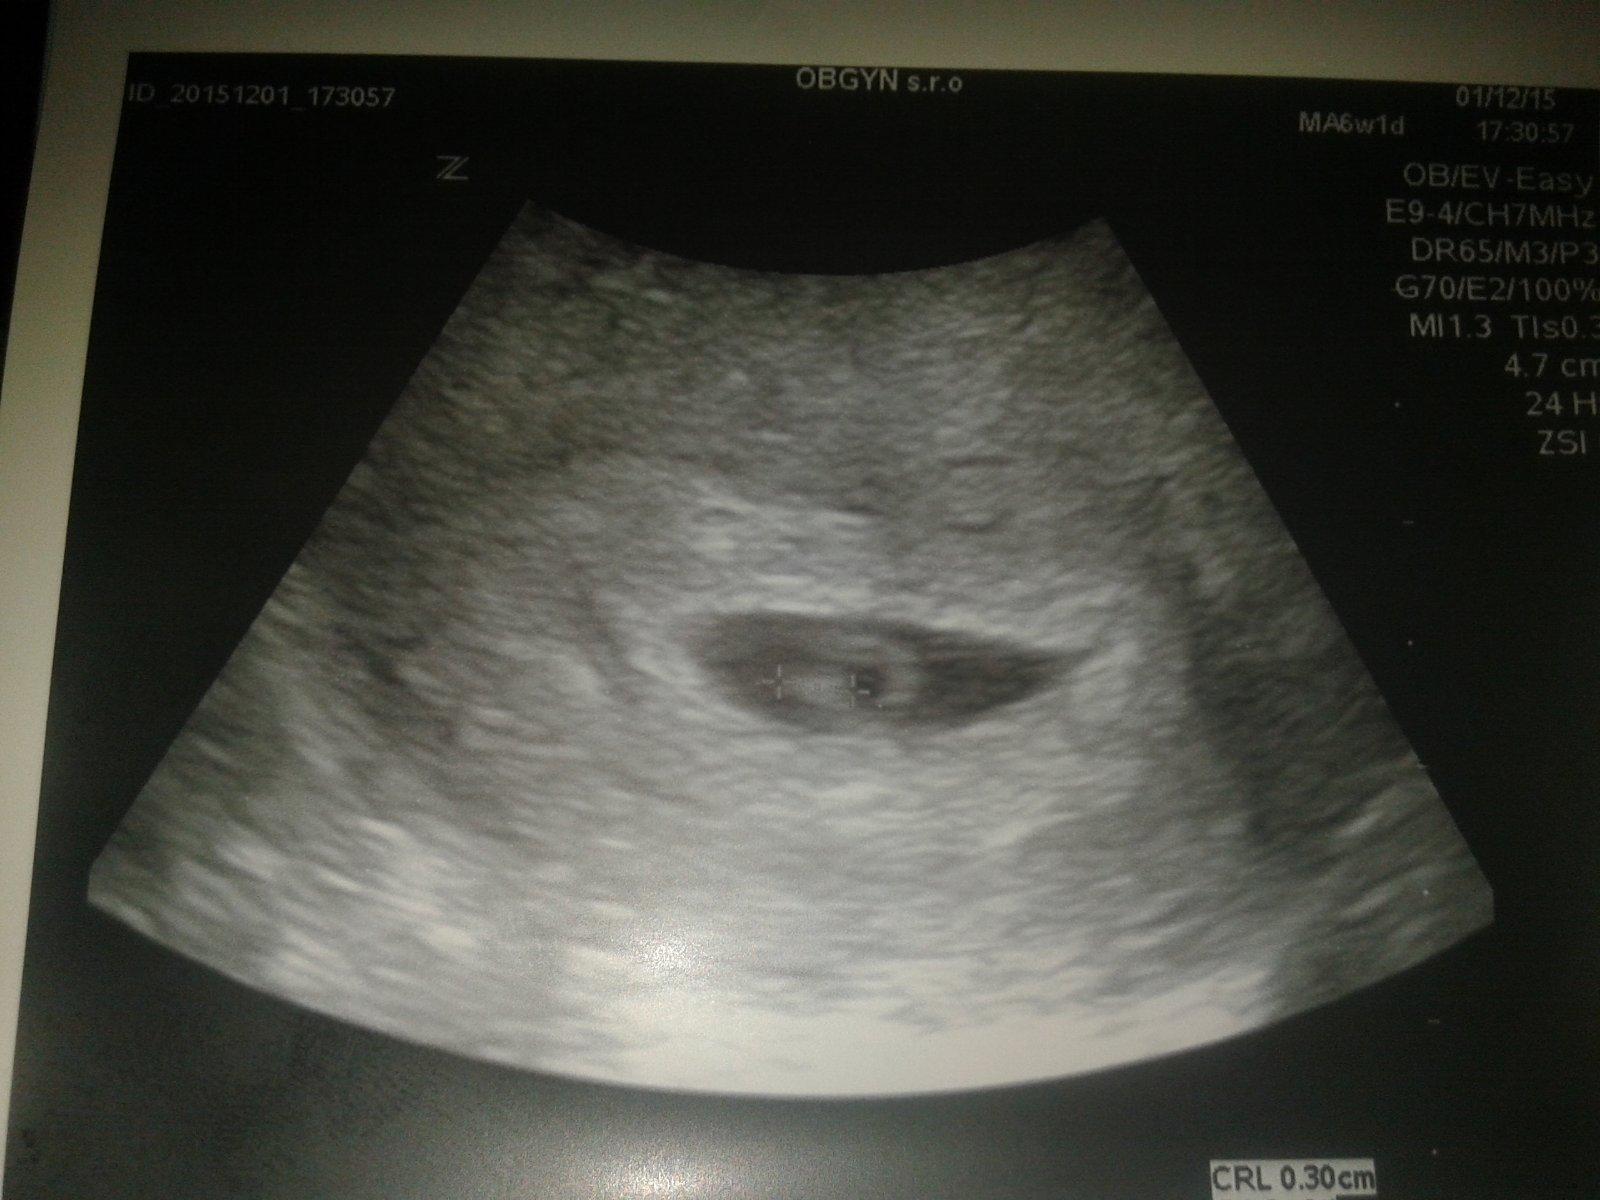

@misella1288 len takto sa mi to da poslat 🙂 drobec malinky 🙂